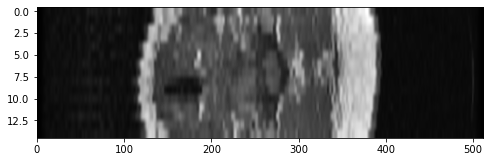

plt.imshow(mri[:, 300, :], cmap="gray", aspect=10)

<matplotlib.image.AxesImage at 0x11358f070>

Here we can see the patient’s wind-pipe as a dark circle on the left side of the image, and a cross-section of their spine in the middle. Or if we wanted to move up a little ways: